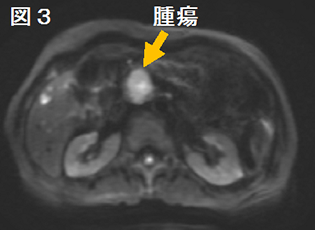

b) CT, MRI検査

膵がんは浸潤する力が強いため、周囲の膵組織との境目がはっきりしないことが多く、CTやMRI(核磁気共鳴検査: 磁石の力で体の中を検査する方法)では判定しにくいことが多いです。膵管が詰まった場合は、流れの悪くなった膵液で膵管が拡がってきますので、それを目安に腫瘍の位置がわかることがあります。MRIでは液体を強調した画像を作ることが出来るため、膵液や胆汁を強調して膵管や胆管への影響を把握することも可能です。最近ではMRIの拡散強調画像という撮影方法によって、腫瘍の硬さから悪性度を判断する方法も行われております。また、肺や肝臓など他の臓器に膵がんが転移していないかも調べることができます。

図2 CT画像

CT画像